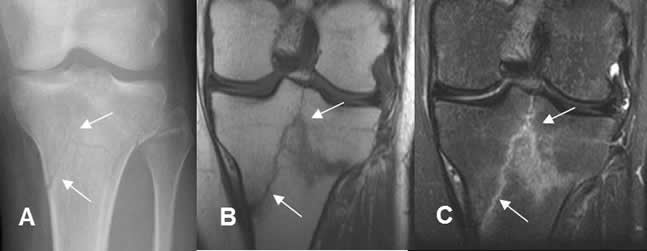

Fig 40. Fractura en “Y”.

A: Rx AP, B: RM coronal en T1 y C: RM coronal en STIR. Fractura conminuta de la tibia proximal, no desplazada y con trazo en “Y”.